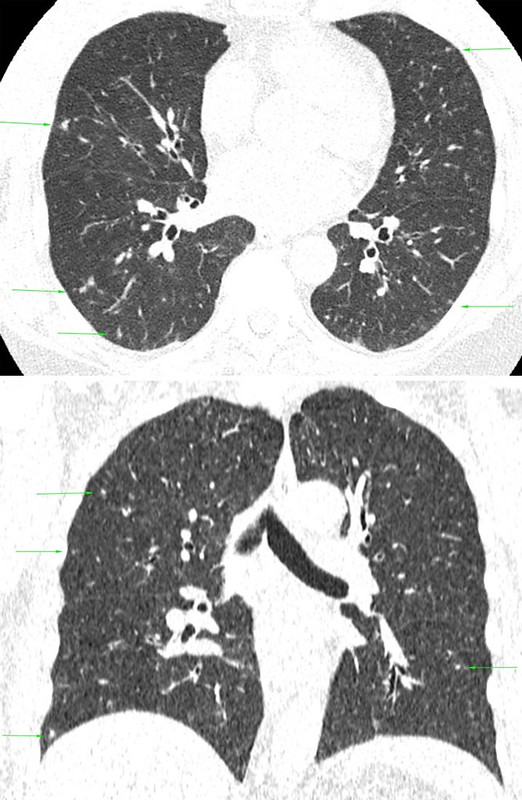

A black and white CT scan shows multiple bilateral soft tissue nodules, many of which demonstrate ground glass attenuation representing thickened bronchioles.